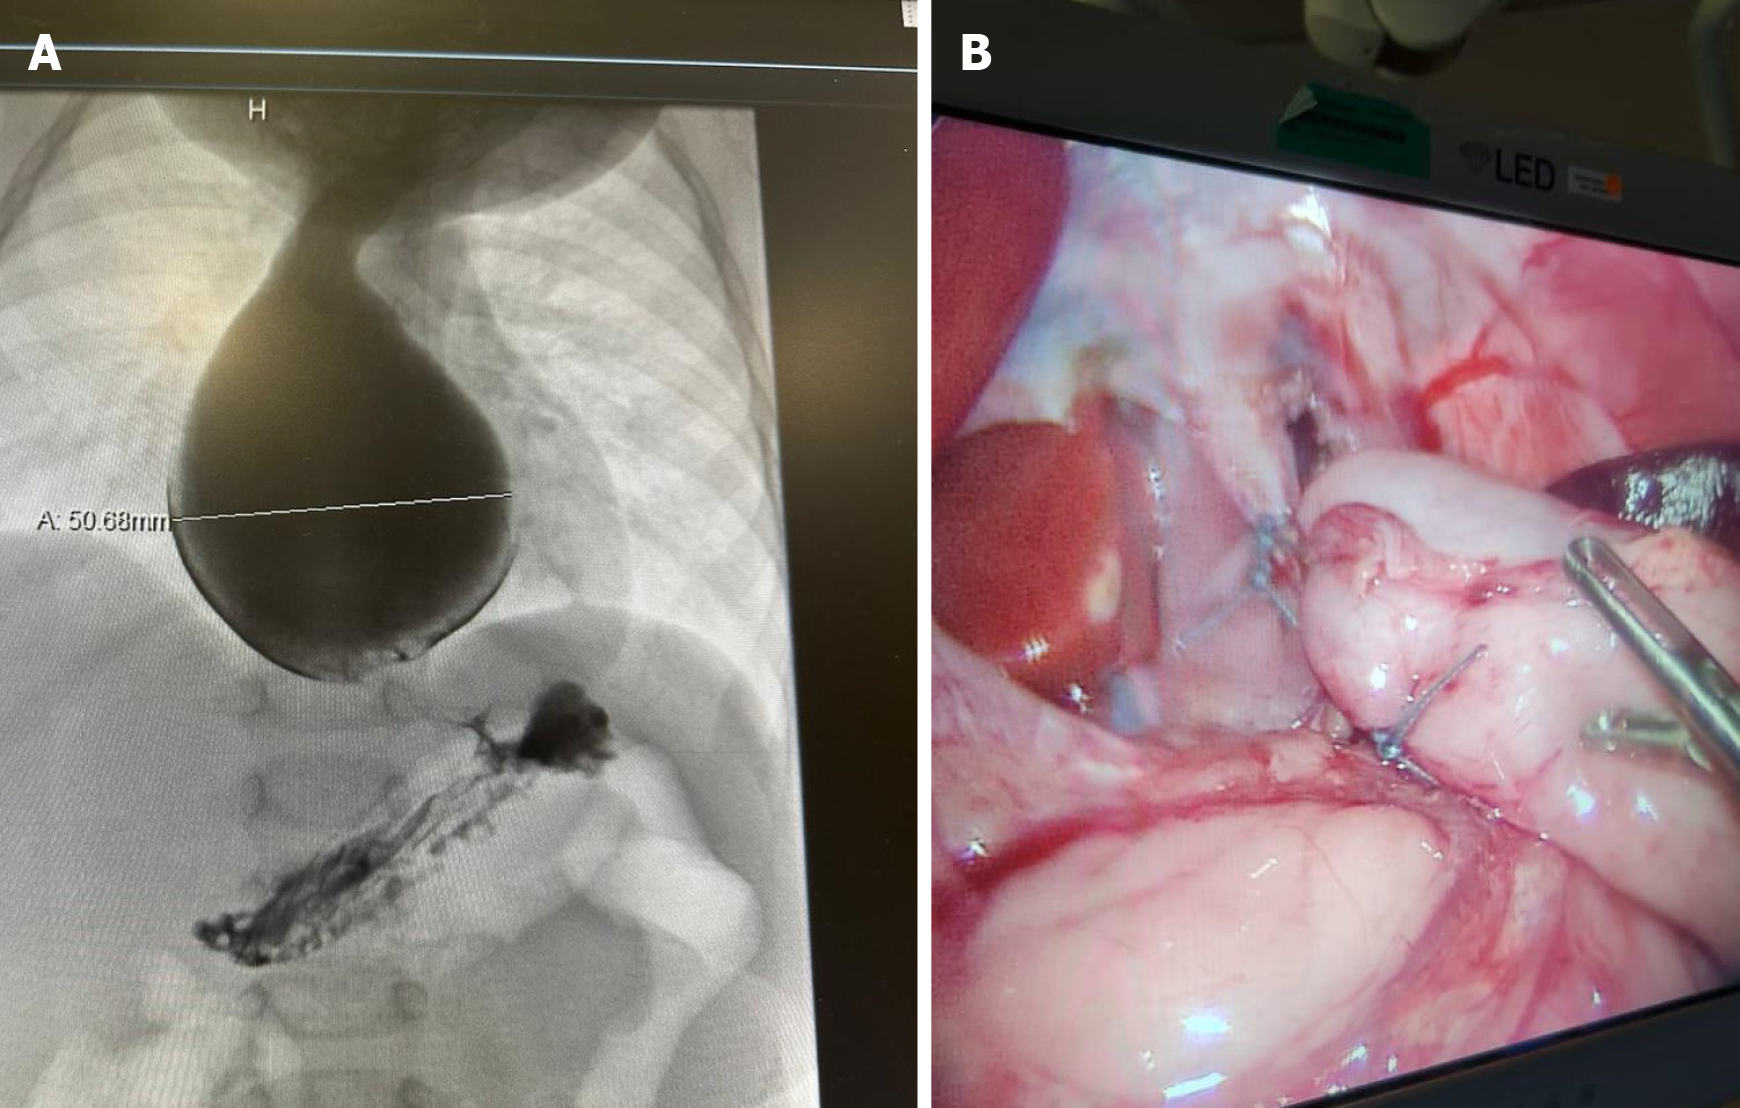

Figure 3 Radiological and surgical images for Case 3.

A: An upper gastrointestinal contrast study showed significant dilation of the esophagus with a pooling of contrast and holdup at the gastroesophageal junction; B: Laparoscopic Heller myotomy was performed.